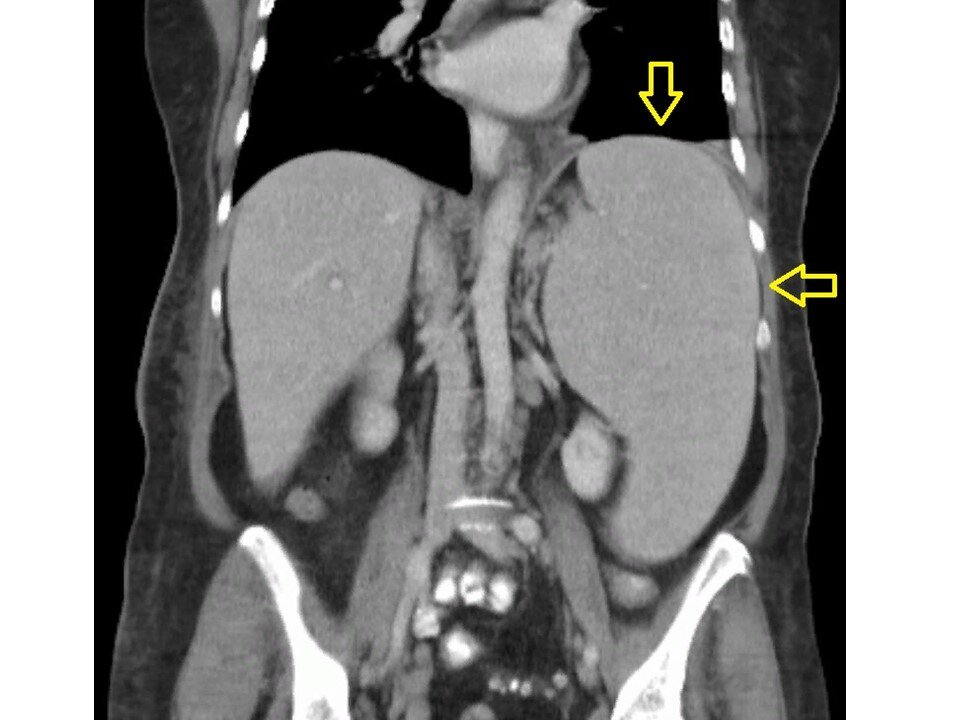

Стрелками отмечена гигантская селезенка

Помню те неистовые ощущения, когда будучи студентом впервые прощупал селезенку. Честно говоря, это смог бы сделать даже простой человек с улицы, потому что ее продольный размер тянулся от левого подреберья до малого таза. Это был пациент с хроническим лимфолейкозом - онкологическим заболеванием крови.

С тех времен прошло немало времени, но таких огромных селезенок мне больше не попадалось, а вот с умеренным увеличением органа встречаться приходилось.

Напомню, что селезенка находится в области левого подреберья, и она выполняет ряд важных функций: очищение крови от старых клеток, участие в поддержании иммунитета, а также в ней находится резерв крови, который может высвобождаться и при необходимости поступать в кровеносное русло, например при интенсивной физической нагрузке или кровопотере.